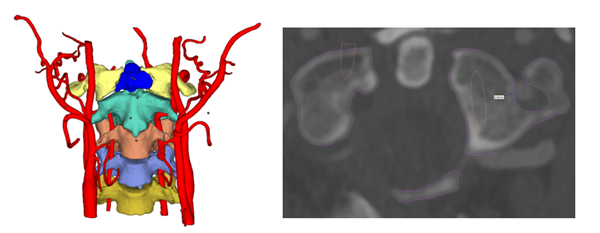

△患者三維重建圖及CT報告

患者2CT示脊柱側(cè)彎畸形。

△患者三維重建圖